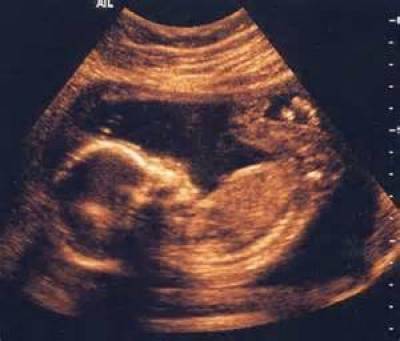

Ανακάλυψε την Αυχενική Διαφάνεια, δηλαδή την εξέταση με υπέρηχο που εφαρμόζεται στον τρίτο μήνα της εγκυμοσύνης προκειμένου να εκτιμηθεί η πιθανότητα το έμβρυο να πάσχει από σύνδρομο Down. Ο ίδιος πραγματοποιεί μικροχειρουργικές επεμβάσεις εντός της μήτρας, σώζοντας τη ζωή εμβρύων που σε διαφορετική περίπτωση δεν θα επιβίωναν. Εχει διδάξει σε εκατοντάδες γιατρούς απ’ όλο τον κόσμο την «τέχνη» του. Καθηγητής στο Τμήμα Εμβρυϊκής Ιατρικής του King’s College του Λονδίνου και πρωτοπόρος ερευνητής για περισσότερα από 30 χρόνια, ο κ. Κύπρος Νικολαΐδης, ο πατέρας της ιατρικής του Εμβρύου όπως τον αποκαλούν, βρέθηκε για μία ημέρα στην Αθήνα προκειμένου να μιλήσει για τις νέες εξελίξεις στον τομέα του. Λίγο πριν ξεκινήσει την ομιλία του στους γιατρούς που είχαν συγκεντρωθεί στην αίθουσα του μαιευτηρίου ΡΕΑ –το οποίο διοργάνωσε και τη σχετική εκδήλωση– εξηγεί σε συναδέλφους του τις συνθήκες εργασίας του στην Αγγλία.